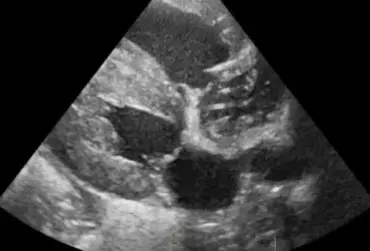

Echo serca z widoczną obecnością dużej liczby nicieni w prawym przedsionku serca (2)

16 kwietnia 2019

Wojciech Atamaniuk

Czytaj więcej